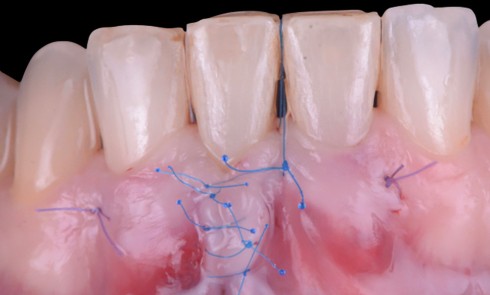

► Il était une fois une amie, médecin, qui présentait des récessions gingivales de 34 à 36. La sensibilité thermique de ces récessions indiquait un recouvrement par une technique de chirurgie plastique parodontale (fig. 1 et 2).

Face aux récessions de classe 1 de Cairo [1] et en présence d’un vestibule relativement profond, une technique de recouvrement radiculaire par lambeau positionné coronairement selon Zucchelli et De Sanctis [2] associé à un greffon conjonctif est choisie.

Cette technique permet de recouvrir des récessions gingivales contiguës par une traction coronaire après une dissection partielle superficielle au-delà de la ligne muco-gingivale. Grâce à un jeu d’incisions des papilles, les incisions de décharge ne sont pas nécessaires. Un greffon conjonctif prélevé au palais selon la technique de l’enveloppe [3] est placé sur les récessions et suturé en même temps que le lambeau par des points suspendus [4].

Dans notre cas clinique, l’intervention a duré un peu moins d’une heure.